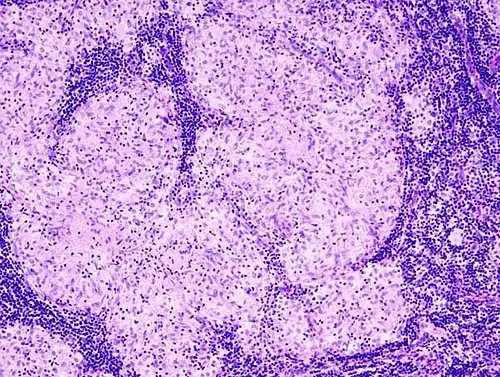

Histopathology

Sarcoidosis is characterized by the formation of non-necrotizing ("non-caseating") granulomas in various organs and tissues.[95] Giant cells, specifically Langhans giant cells, are often seen in sarcoidosis.[96] Schaumann bodies seen in sarcoidosis are calcium and protein inclusions inside of giant cells as part of a granuloma.[97] Asteroid bodies can be seen in sarcoidosis.[97] Hamazaki–Wesenberg bodies can be seen in lymph nodes and more rarely in lung biopsies with sarcoidosis and are inclusion bodies of lysosomes with protein, glycoprotein and iron.[98]